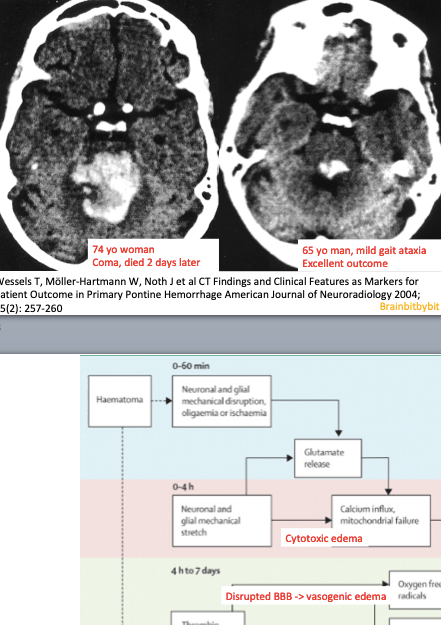

In the hindbrain or rhombencephalon, consisting of pons and medulla oblongata, vital functions are interdispersed with cranial nerve nuclei and ascending and descending tracts. Because of intermixed gray and white matter the pons is especially vulnerable to osmotic demyelination (45). The diverse neurological and psychiatric symptoms observed in patients with pontine osmotic demyelination reflect the different and divergent functions of this region. The brain’s main noradrenaline synthesis site is located in the dorsal pons, the locus coeruleus. From the rostral to the caudal hindbrain, raphe nuclei along the midline contain the majority of serotonergic neurons. The medulla oblongata or bulbus, houses the cardiovascular and respiratory center.